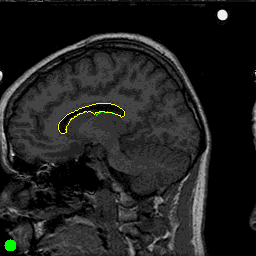

You may read this html paper for more information about a neural network's ability to do non-linear discriminations for boundary detection. The user starts a trace using the mouse. When enough examples have been collected, the disk in the lower left corner goes green (it was red). Then the user can let go of the mouse. At this point, two things happen. A neural net is trained to recognize the traced pixels as boundary pixels and the resulting neural net is used to automatically continue the trace for a fixed number of pixels. The manually-traced pixels are in green and the automatically-traced pixels are in yellow. The user now has the option of using the trained net for further tracing or training a new net.

Here are some examples using MRI images of the brain from two subjects.

First we manually traced the cortex of the brain, starting with

the green pixels to the lower left. Then, we used the trained neural network to continue

tracing. The short green segments are the manual tracings, and the yellow

segments show the net's continuations.